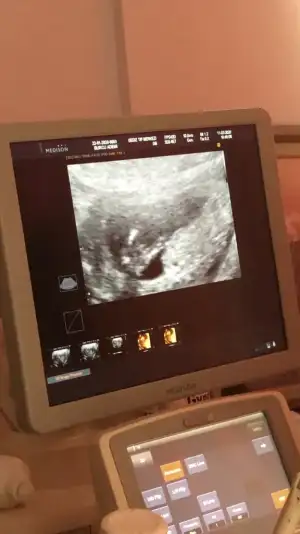

İlk iki foto alttan bakılandan son foto normal daha öncede atmıstım ama cok belli değil demiştiniz bu şekilde bi tahmin olabilirmi Ikra meyra Ikra meyra ☺️